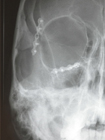

Clichés 2D de contrôle après réduction synthèse par plaque et greffe osseuse: